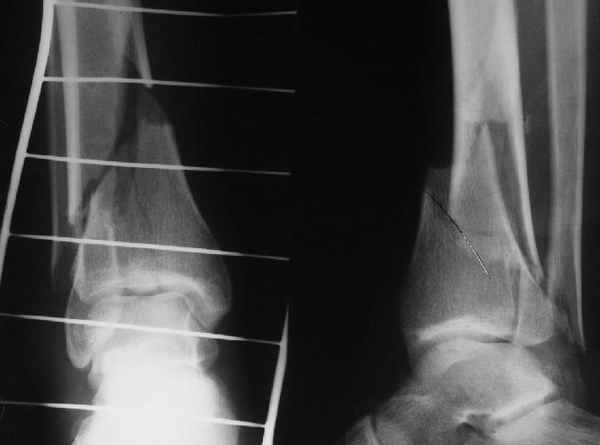

В приложении остеосинтез перелома шейки плеча LPHP у доктора из нашей клинике , через 8недель уже трудился в операционной

Кликните для загрузки файла 06.JPG

АМ> В приложении остеосинтез перелома шейки плеча LPHP у доктора из нашей

АМ> клинике, через 8недель уже трудился в операционной

Очень симпатично, спору нет, но полагаю, что и с Y-спицами полная реабилитация к этому сроку была бы вполне реальна.